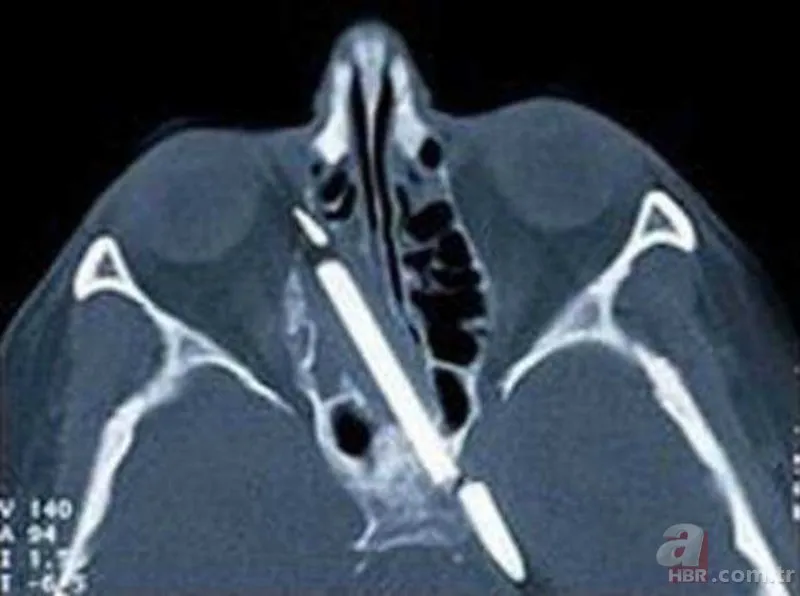

Bir inşaat işçisi bir gün doktora gitti. Dişi ağrıyan ve bulanık gördüğünü söyleyen adamın sorunu ise 20 yaş dişi değildi. Kafatasında bir çivi bulunan adam, bir hafta önce çivi makinesi ile çalışırken bir sorun yaşamıştı. makine tepmiş, adamın ağzından içeri bir çivi göndermiş ve bu çivi kafatasına kadar gitmişti!